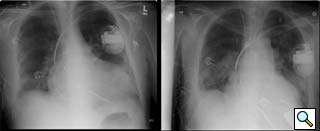

Figure 9: Pre- and postoperative chest radiographs in a 6’7” male demonstrating ventricular decompression.

- Some will argue that the output of continuous flow pumps like the Jarvik 2000 is inadequate for certain patients. Although intrathoracic placement of the Heartmate pump has been described [9], pump size limits this approach to larger patients. The Jarvik 2000 has provided reliable and sufficient outputs for all of our patients (Figure 9 is a pre and postoperative CXR showing LV decompression in a patient that was 6’7” with a body surface area of nearly 2.3). That said, the Jarvik 2000 is an assist, and not replacement device.